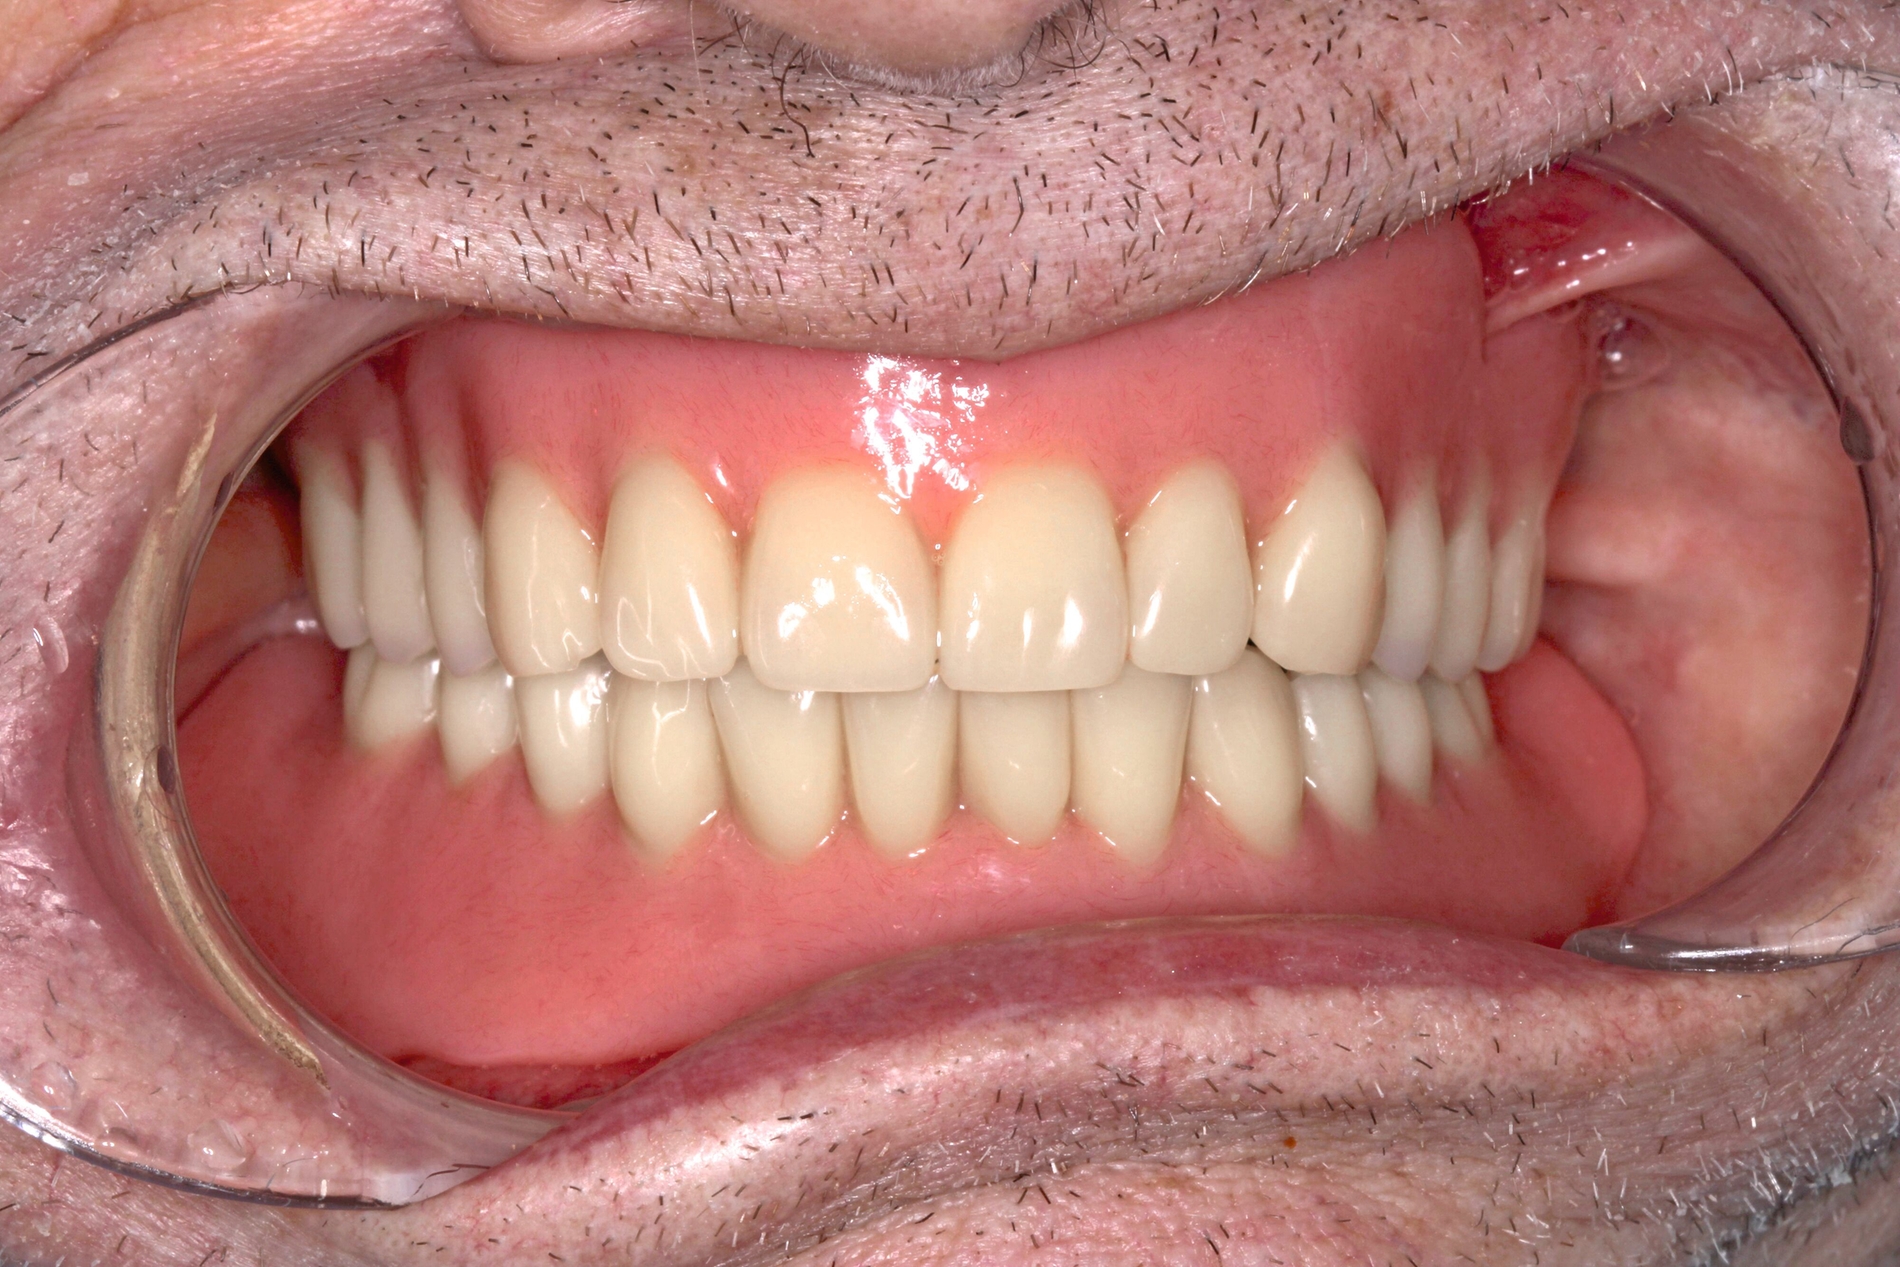

Patientinnen und Patienten mit stark reduzierter Therapiefähigkeit profitieren in besonderem Maß von zeiteffektiven Methoden und Materialien, zum Beispiel Bulk-fill-Kompositen, Reparaturfüllungen, Glasionomerzementen oder Intraoralscans. Die Therapiefähigkeit kann – ähnlich wie in der Kinderzahnmedizin – durch ein vertrauensvolles Verhältnis optimiert werden. Anders als in der Kinderzahnmedizin gibt es in der Alterszahnmedizin aber keine altersassoziierten Kontraindikationen für zahnmedizinische Interventionen. Voraussagbare Therapieergebnisse sind von besonderer Bedeutung, um erneute Behandlungen zu vermeiden. Das gesamte Spektrum zahnmedizinischer Interventionen kann bei der Behandlung von Personen mit Pflegebedarf sinnvoll sein. Die Abbildungen 6 bis 9 zeigen zahnmedizinische Interventionen bei Personen mit ausgeprägter Frailty (Stufe 7 der klinischen Frailty-Skala).